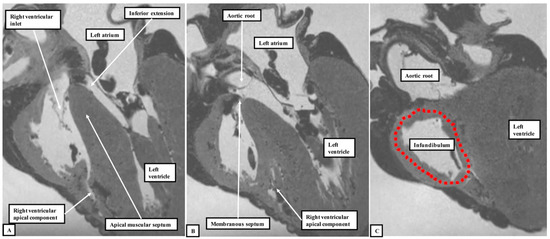

We have now validated our examinations made on the basis of dissection by using high-resolution magnetic resonance imaging of an intact autopsy specimen prior to its subsequent dissection. Thus, in Figure 3, we show the view of the right ventricle of the same heart we used to produce Figure 1. In Figure 4, we show sectional images through the heart obtained from the three-dimensional dataset of the heart produced by interrogation using a 7 Tesla magnetic resonance scanner prior to dissection.

Figure 4. Panels A through C show the images obtained by scanning the heart photographed in Figure 1 and Figure 3 using magnetic resonance imaging prior to subsequent dissection. They show that, by virtue of the inferior extension of the subaortic outflow tract, the apical muscular ventricular septum separates the inlet of the right ventricle from the outlet of the left ventricle. They also reveal that the subpulmonary infundibulum is a myocardial sleeve, as shown by the dotted red oval in panel C.